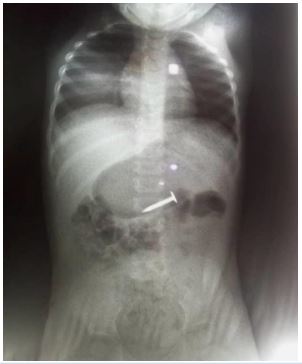

She presented with a plain abdominal radiograph which showed a FB (nail) in the body of the stomach (Figure 1) This was done about 6 hours prior to the presentation at our facility. A repeat radiograph done at the presentation showed the FB (nail) at the region of the terminal ileum (Figure 2). She was commenced on nil per oral, intravenous fluids and monitoring (clinical and radiological). She had two additional plain abdominal radiographs, (Figure 3, 24 hours on admission) and (Figure 4, on day 3). The vital signs remained stable and the abdominal examinations remained equivocal throughout the period of admission. She was discharged following a repeat radiograph which showed no evidence of FB in the GIT.

Figure 4: AP view of plain abdominal radiograph (Day 3).